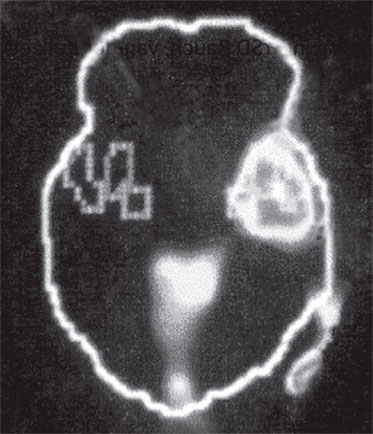

А. Правая лимбическая область

Б. Зрительная кора

В. Зона Брока

Изображение мозга в процессе переживания травмы. Светлые пятна в лимбической коре (А) и зрительной коре (Б) соответствуют повышенной активности мозга в этих участках. На снимке (В) видна значительно пониженная активность речевого центра мозга.

Когда через эту процедуру прошли все восемь участников, Скотт Рауч вместе со своими математиками и статистиками взялся за создание составного снимка, по которому можно было бы наглядно сравнить активность мозга в нейтральном состоянии и в момент появления неприятных воспоминаний. Несколько недель спустя он отправил мне результаты, которые вы видите выше. Я приклеил эти снимки на дверцу своего холодильника в кухне и на протяжении следующих нескольких месяцев каждый вечер их разглядывал. Должно быть, именно так чувствовали себя первые астрономы, взглянув через телескоп на неизученное звездное скопление.

На снимках были некоторые сбивающие с толку точки и цвета, однако самая яркая область активации мозга – большое красное пятно в правом нижнем центре мозга, известном как лимбическая область, или эмоциональный мозг, – никакого удивления не вызывала. Мы уже знали, что сильные эмоции активируют лимбическую систему, в особенности участок внутри нее, известный как миндалевидное тело.

Миндалевидное тело предупреждает нас о надвигающейся опасности, активируя стрессовую реакцию организма. Наше исследование явно показало, что у переживших травму людей определенные образы, звуки или мысли, связанные с их конкретными переживаниями, миндалевидное тело начинает бить тревогу – даже, как это было в случае с Маршей, спустя тринадцать лет после самого происшествия.

Больше всего из полученных нами результатов нас поразила белая точка в левой фронтальной доле коры, так называемой зоне Брока. В данном случае изменение цвета означает значительный спад активности в этой области мозга.

Зона Брока – это один из речевых центров мозга, который зачастую бывает затронут у людей, перенесших инсульт, когда этот участок оказывается отрезан от кровотока. Без нормально функционирующей зоны Брока человек неспособен выражать словами свои мысли и чувства. Наши снимки показали, что при активации болезненных воспоминаний зона Брока отключалась.

Когда слова подводят, центральное место в переживаниях занимают навязчивые образы, которые впоследствии преследуют нас в виде ночных кошмаров и болезненных живых воспоминаний. Если у наших участников отключалась зона Брока, то другой участок мозга под названием поле Бродмана 19[16] в этот момент активировался. Эта область зрительной коры регистрирует образы, когда они впервые попадают в мозг. Мы были удивлены увидеть активацию этой области спустя столь долгое время после изначально пережитой травмы. Обычно необработанные образы, зарегистрированные в поле 19, быстро распределяются по остальным участкам мозга, которые пытаются осмыслить увиденное. Опять-таки, мы стали свидетелями того, как участок мозга зажигается, словно человек переживает свою психологическую травму прямо сейчас.

Снимки также показали, что во время этих живых болезненных воспоминаний у наших подопытных активировалась лишь правая часть мозга. В настоящий момент имеется множество научной и популярной литературы на тему различий между правым и левым полушарием. В начале девяностых мне доводилось слышать, что кто-то начал делить мир на людей с развитым левым (преобладает рациональное мышление, логика) и правым (интуиция, творческие способности) полушариями, однако тогда я не придал этой идее особого значения. Тем не менее наши снимки явно демонстрировали, что образы о пережитой травме активируют правое полушарие мозга, отключая при этом левое.